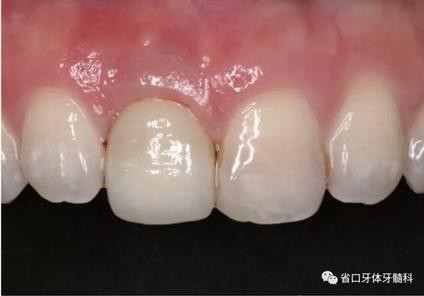

圖30 塑形完成

(4)最終修復(fù)與隨訪:經(jīng)過(guò)3個(gè)月左右的塑形,上頜右側(cè)中切牙臨時(shí)修復(fù)固位良好,菌斑控制良好,近遠(yuǎn)中齦乳頭充盈良好,齦緣水平及形態(tài)與 鄰牙相對(duì)稱。牙齦塑形穩(wěn)定后,以臨時(shí)修復(fù)體制作個(gè)性化轉(zhuǎn)移桿并取模轉(zhuǎn)移,并以原廠氧化鋯基臺(tái)制備個(gè)性化基臺(tái)及全瓷冠。正確就位最終基臺(tái),加 力30N·cm。制備粘接代型,去除多余粘接劑,以Unicem粘接固位上頜右側(cè)中切牙全瓷修復(fù)體。固化穩(wěn)定后,再次確定咬合無(wú)干擾。最終修復(fù)完成后 隨訪3個(gè)月及6個(gè)月,上頜右側(cè)中切牙種植修復(fù)固位穩(wěn)定,近遠(yuǎn)中齦乳頭充 盈良好,唇側(cè)齦緣水平穩(wěn)定。

(3)術(shù)后醫(yī)囑與牙齦塑形:術(shù)后予以抗炎止痛對(duì)癥處理,7~10天拆 線。術(shù)后3個(gè)月開(kāi)始逐步調(diào)整臨時(shí)冠并塑形牙齦形態(tài),控制上頜右側(cè)中切牙 近遠(yuǎn)中牙齦乳頭的充盈量和齦緣水平,使得上頜右側(cè)中切牙牙齦形態(tài)與上頜 左側(cè)中切牙盡量相對(duì)稱。